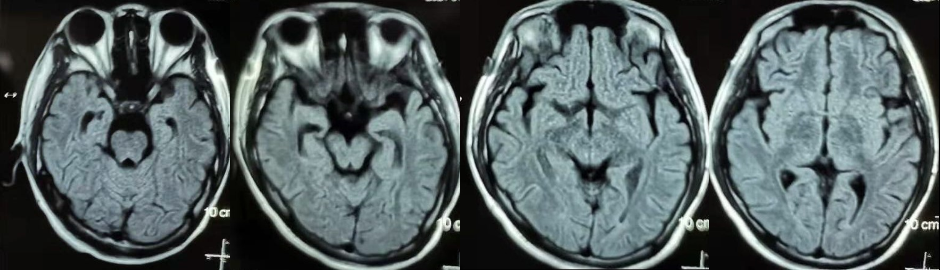

辅助检查:2021年01月18日我院查颅脑MRI+DWI示:未见明显异常,建议随诊复查(见图2)。查眼震电图示:凝视时诱发上跳眼震,峰值在23°~46°之间(见图3)。

图2 头颅MRI(2021年01月18日 )